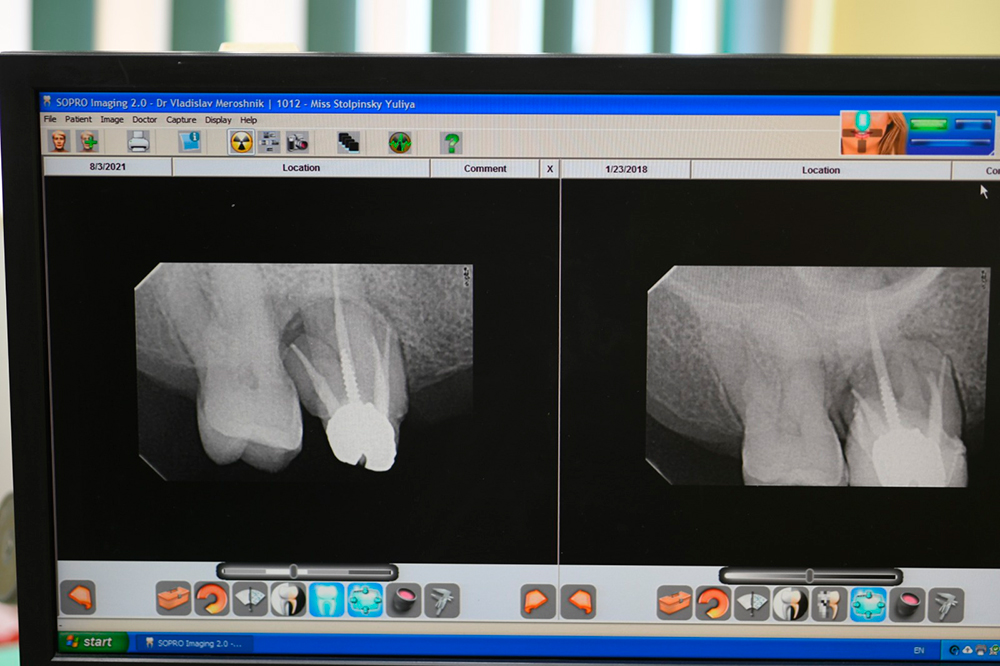

Rare documented case from 2017 to 2021 - bone regrowth after cleaning, curretage and applying DSI Syntoss Plus

Dear colleagues, I would like to share a clinical case that I have been observing since 2017. A patient came to the clinic with complaints of swelling and pain in the area 1.3, 1.4, 1.5. Conservative therapy was suggested, and after dealing with the acute period, a surgical procedure including cleaning of the periodontal pocket, scaling and root planing and filling the bone pocket with DSI Syntoss Plus that contains beta-tricalcium phosphate granules. The procedure was performed in 2017, the old bridge was replaced with a new one, which is fixed with temporary cement for regular revision due to the unstable condition of 2.6. The patient is unable to undergo implantation for a number of reasons, so the 2.6 will be kept until the last possible moment. Its mobility is grade 2 and the condition of the mucosa can be seen in the photo. The whole process of bone maturation is shown on the x-rays. Thank you for your attention.